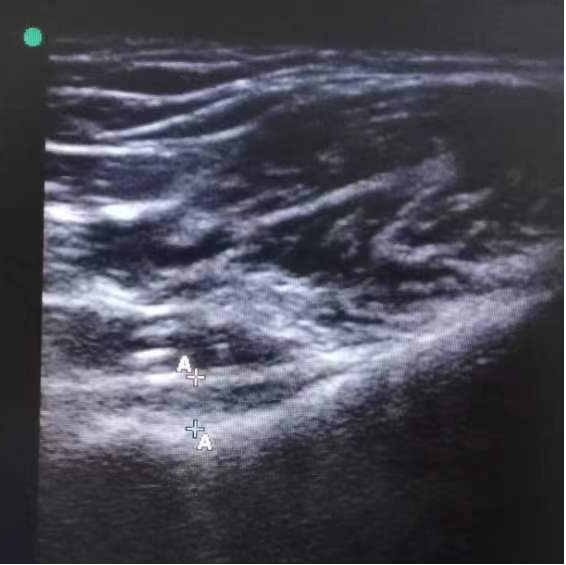

特色技術(shù):超聲引導(dǎo)下肩關(guān)節(jié)囊液壓擴(kuò)張手法松解術(shù)

超聲引導(dǎo)下肩關(guān)節(jié)囊液壓擴(kuò)張手法松解術(shù)是一種結(jié)合超聲影像實(shí)時引導(dǎo)與液壓擴(kuò)張?jiān)淼奈?chuàng)治療技術(shù),主要用于粘連性肩關(guān)節(jié)囊炎的治療。

高頻超聲探頭可清晰顯示肩關(guān)節(jié)囊的結(jié)構(gòu),動態(tài)監(jiān)測穿刺針位置,確保液體精準(zhǔn)注入目標(biāo)區(qū)域,避免損傷血管、神經(jīng)及肌腱。